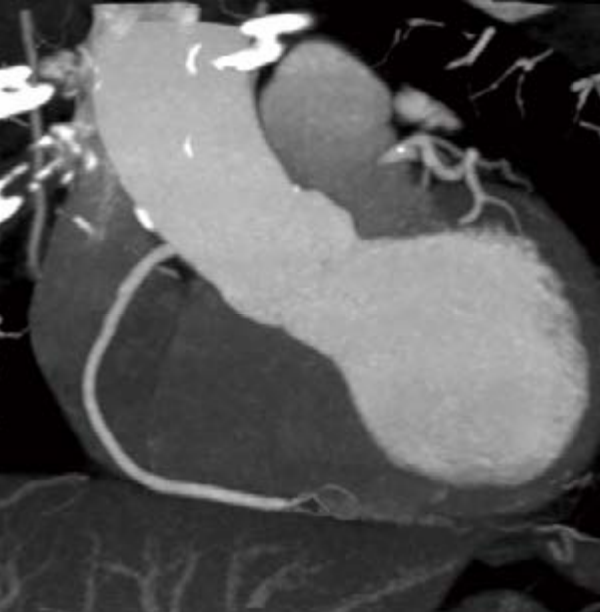

SinoVision Insitum 64s - это 64 срезовый КТ с большой апертурой гентри 75см. Один из самых доступных кардиологических компьютерных томографов. SinoVision Insitum 64 - это 64 срезовый КТ с большой апертурой гентри 76см. Уникальная интеллектуальная система управления стробированием SinoVision и алгоритм реваскуляризации коронарных артерий гарантируют мгновенное замораживание сердца и отображение структуры сердечно-сосудистой системы, стента, кальцификации, бляшек и другой информации в высоком разрешении.

- Интеллектуальная платформа коронарной визуализации мгновенно замораживает сердце и отображает информацию высокого разрешения о сердечно-сосудистых структурах, стентах, кальцификации и бляшках с помощью уникальной интеллектуальной системы управления и алгоритмов коронарной реваскуляризации SinoVision.

- Изображения процесса замораживания коронарной артерии в режиме реального времени

- Расширенный коронарный анализ

- Определяет степень стеноза и состав бляшки коронарной артерии, помогает при послеоперационном осмотре при шунтировании и стентировании

- Анализ стеноза коронарной артерии

- Удаление и измерение коронарных артерий с помощью искусственного интеллекта